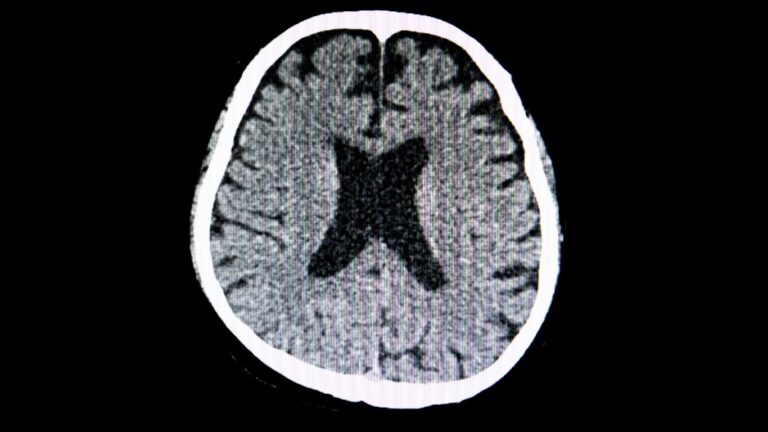

La tomografía de cráneo representa una herramienta fundamental en el ámbito de la medicina moderna. Este procedimiento permite obtener imágenes de alta resolución del cerebro y el cráneo, facilitando el diagnóstico cerebral de diversas condiciones. Ante la creciente demanda por diagnósticos precisos, comprendemos la importancia de la tomografía de cráneo para identificar trastornos neurológicos y lesiones traumáticas.

Al utilizar rayos X, la tomografía ofrece una visualización detallada, permitiendo a los médicos tomar decisiones informadas sobre el tratamiento adecuado para cada paciente. Esta técnica no solo mejora la calidad del diagnóstico, sino que también optimiza la planificación de intervenciones médicas. En un mundo donde el tiempo es esencial, recurrir a la tomografía de cráneo se convierte en una opción valiosa para garantizar una atención oportuna y efectiva.

La tomografía computarizada de cráneo es una técnica de imagen que utiliza radiación para capturar imágenes detalladas de la estructura del cráneo. Este procedimiento se basa en la tecnología avanzada para proporcionar una visión tridimensional, permitiendo la identificación precisa de diversas patologías. A través de este examen, podemos detectar condiciones críticas como hemorragias, tumores y fracturas que podrían afectar la salud del paciente.

La relevancia de esta técnica de imagen radica en su capacidad para ofrecer información valiosa que influye en el tratamiento y el diagnóstico médico. Al realizar una tomografía computarizada de cráneo, los médicos obtienen un panorama completo que les ayuda a tomar decisiones informadas sobre el cuidado del paciente.